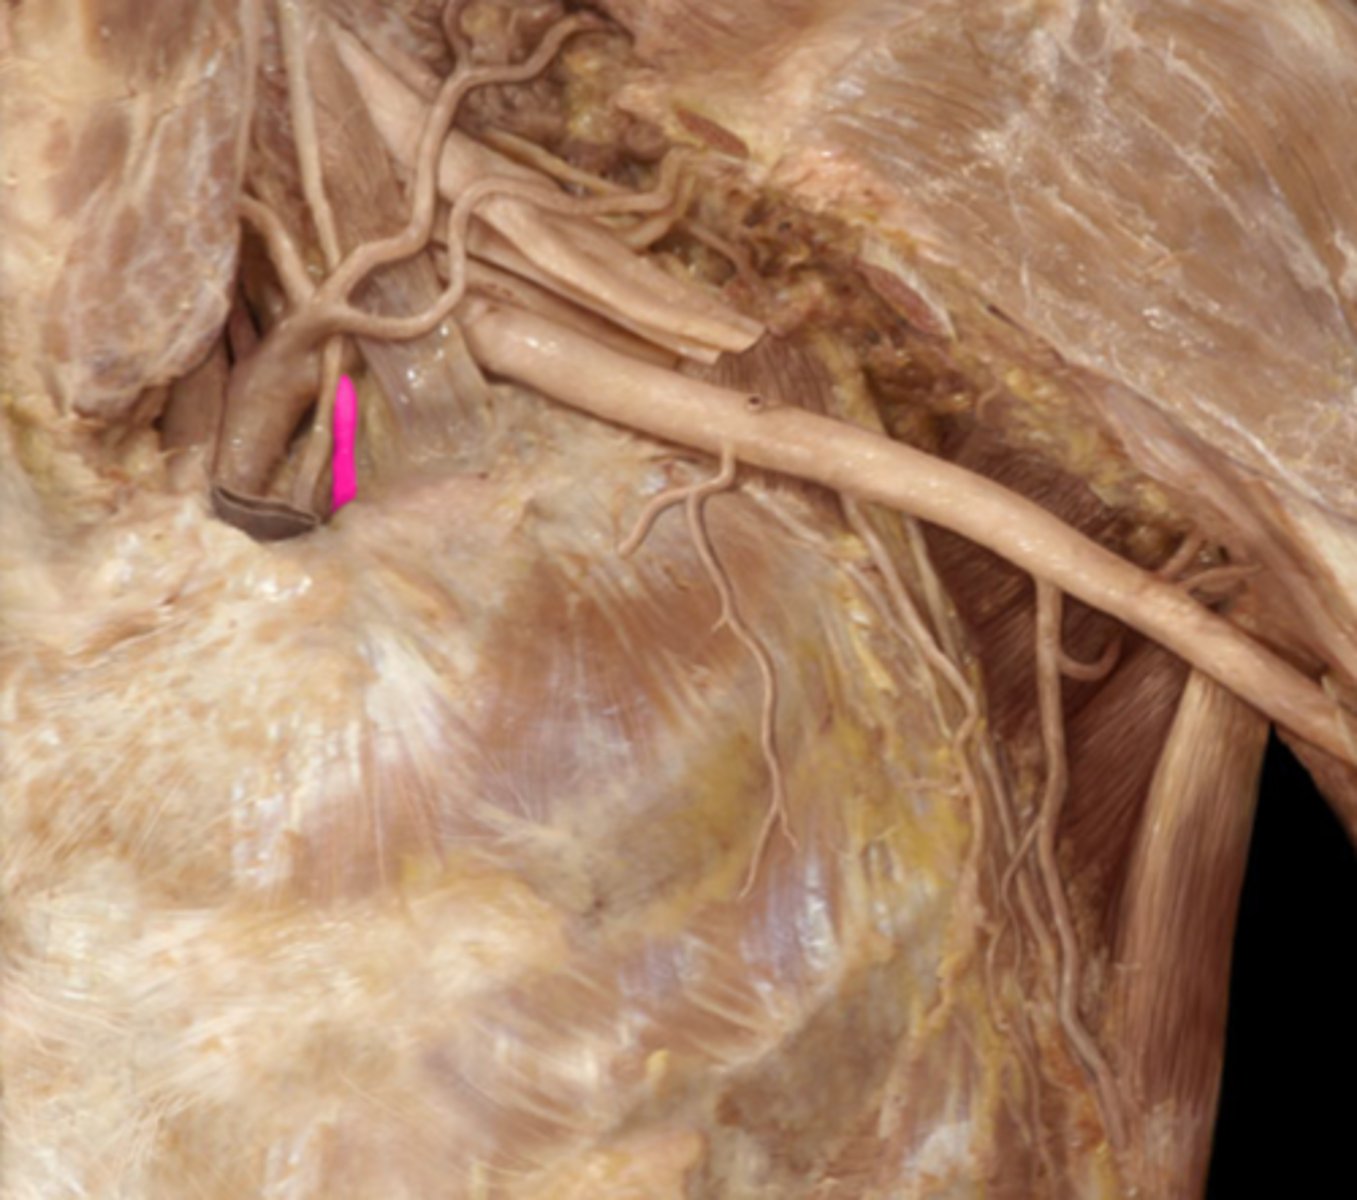

Identify the vessel

right pulmonary artery

ligamentum arteriosum

vestige of the fetal ductus arteriosus, which shunted blood in the pulmonary trunk away from the lungs in the fetus